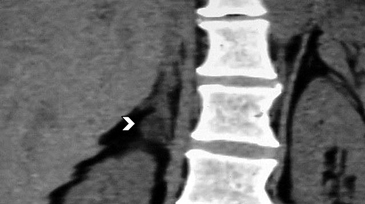

Los sitios más habituales de metástasis son hígado, pulmón, además de la invasión de las estructuras vasculares adyacentes, especialmente de la vena cava inferior, hallazgo que constituye una consideración fundamental al momento de planificar el abordaje quirúrgico (Figura 23 a y b).

Figura 23. Carcinoma suprarrenal derecho. Corte axial de resonancia magnética ponderado en T2 con saturación grasa (a) en que se demuestra una masa suprarrenal derecha con áreas hiperintensas en su espesor probablemente determinadas por necrosis (flecha) y corte coronal en secuencia TRUFISP (b) en que se observa un trombo tumoral que expande el lumen de la vena cava inferior (cabeza de flecha).Puede también presentar invasión directa de otras estructuras vecinas, como riñón, páncreas, bazo y diafragma.